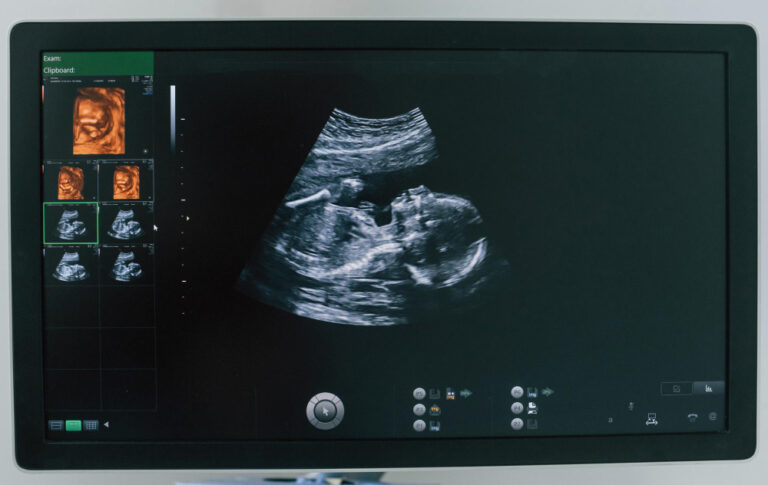

Genetic Sonogram (Ultrasound):This precisely measures the Nuchal Translucency (NT) , which is the clear fluid-filled space at the back of the fetal neck. An increased NT measurement is associated with a higher risk of chromosomal defects and major heart anomalies. The scan also confirms dating and viability.